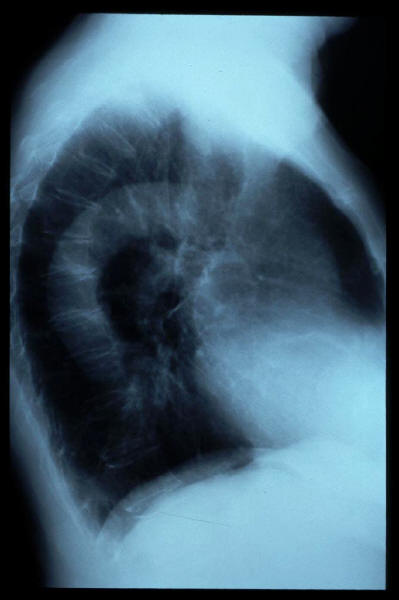

Aerofagia en TEGD.

Aerofagia en TGED.